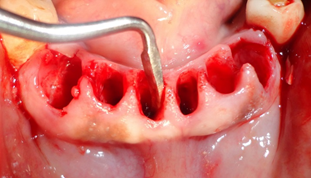

Todos dentes condenados tiveram que ser extraídos. As remoções foram feitas com muita cautela para não haver rompimento da crista óssea, assim como do septo interdental. Esse procedimento deve ser realizado em todas exodontias, para preservar o máximo de tecido ósseo alveolar.

Os dentes depois de extraídos, os alvéolos limpos e curetados rigorosamente. Importantíssimo, netas cirurgias, é realizar os procedimentos como uma cirurgia de retalho periodontal, pois as paredes das bolsas periodontais devem ser totalmente removidas, com uma lâmina número 15, realizando uma incisão de bizel interno, para a remoção total do tecido interno que forma a bolsa, eliminando assim as bactérias infiltradas neste tecido. A exposição de uma mucosa gengival sadia, após o deslocamento do retalho total, é importantíssima, para a cicatrização. A camada basal do epitélio gengival, exposta, tem um enorme potencial de regeneração, o que será importante nas técnicas de Regeneração Óssea Guiada.